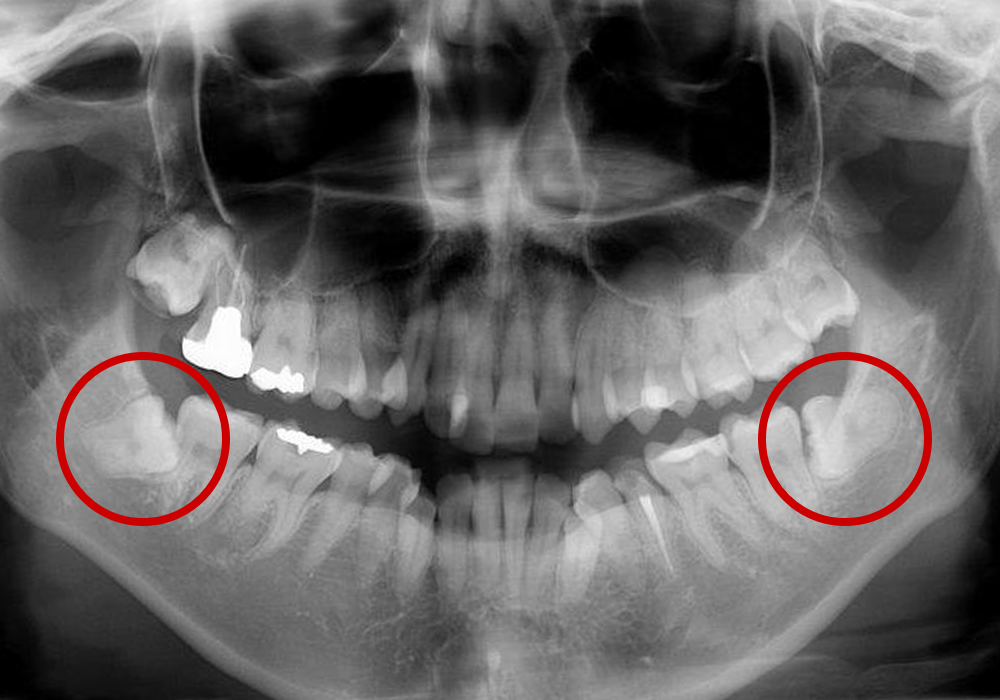

親知らずとは大臼歯(大人の奥歯)の中で一番後ろに位置する第3大臼歯です。智歯とも呼ばれ20歳前後で生えてくることが多く、一般的には上顎の左右2本と下顎の左右2本計4本ありますが、もともと親知らずのない人や4本そろっていない人など、個人差があります。

親知らずが周囲に悪影響をもたらしている場合は、早めの抜歯をおすすめします。

親知らずが横や斜めに生えてきたり、歯ぐきが被っていることがあります。そのため、親知らずの周囲には細菌が残りやすく、以下のようなトラブルを起こし、痛みの原因になります。